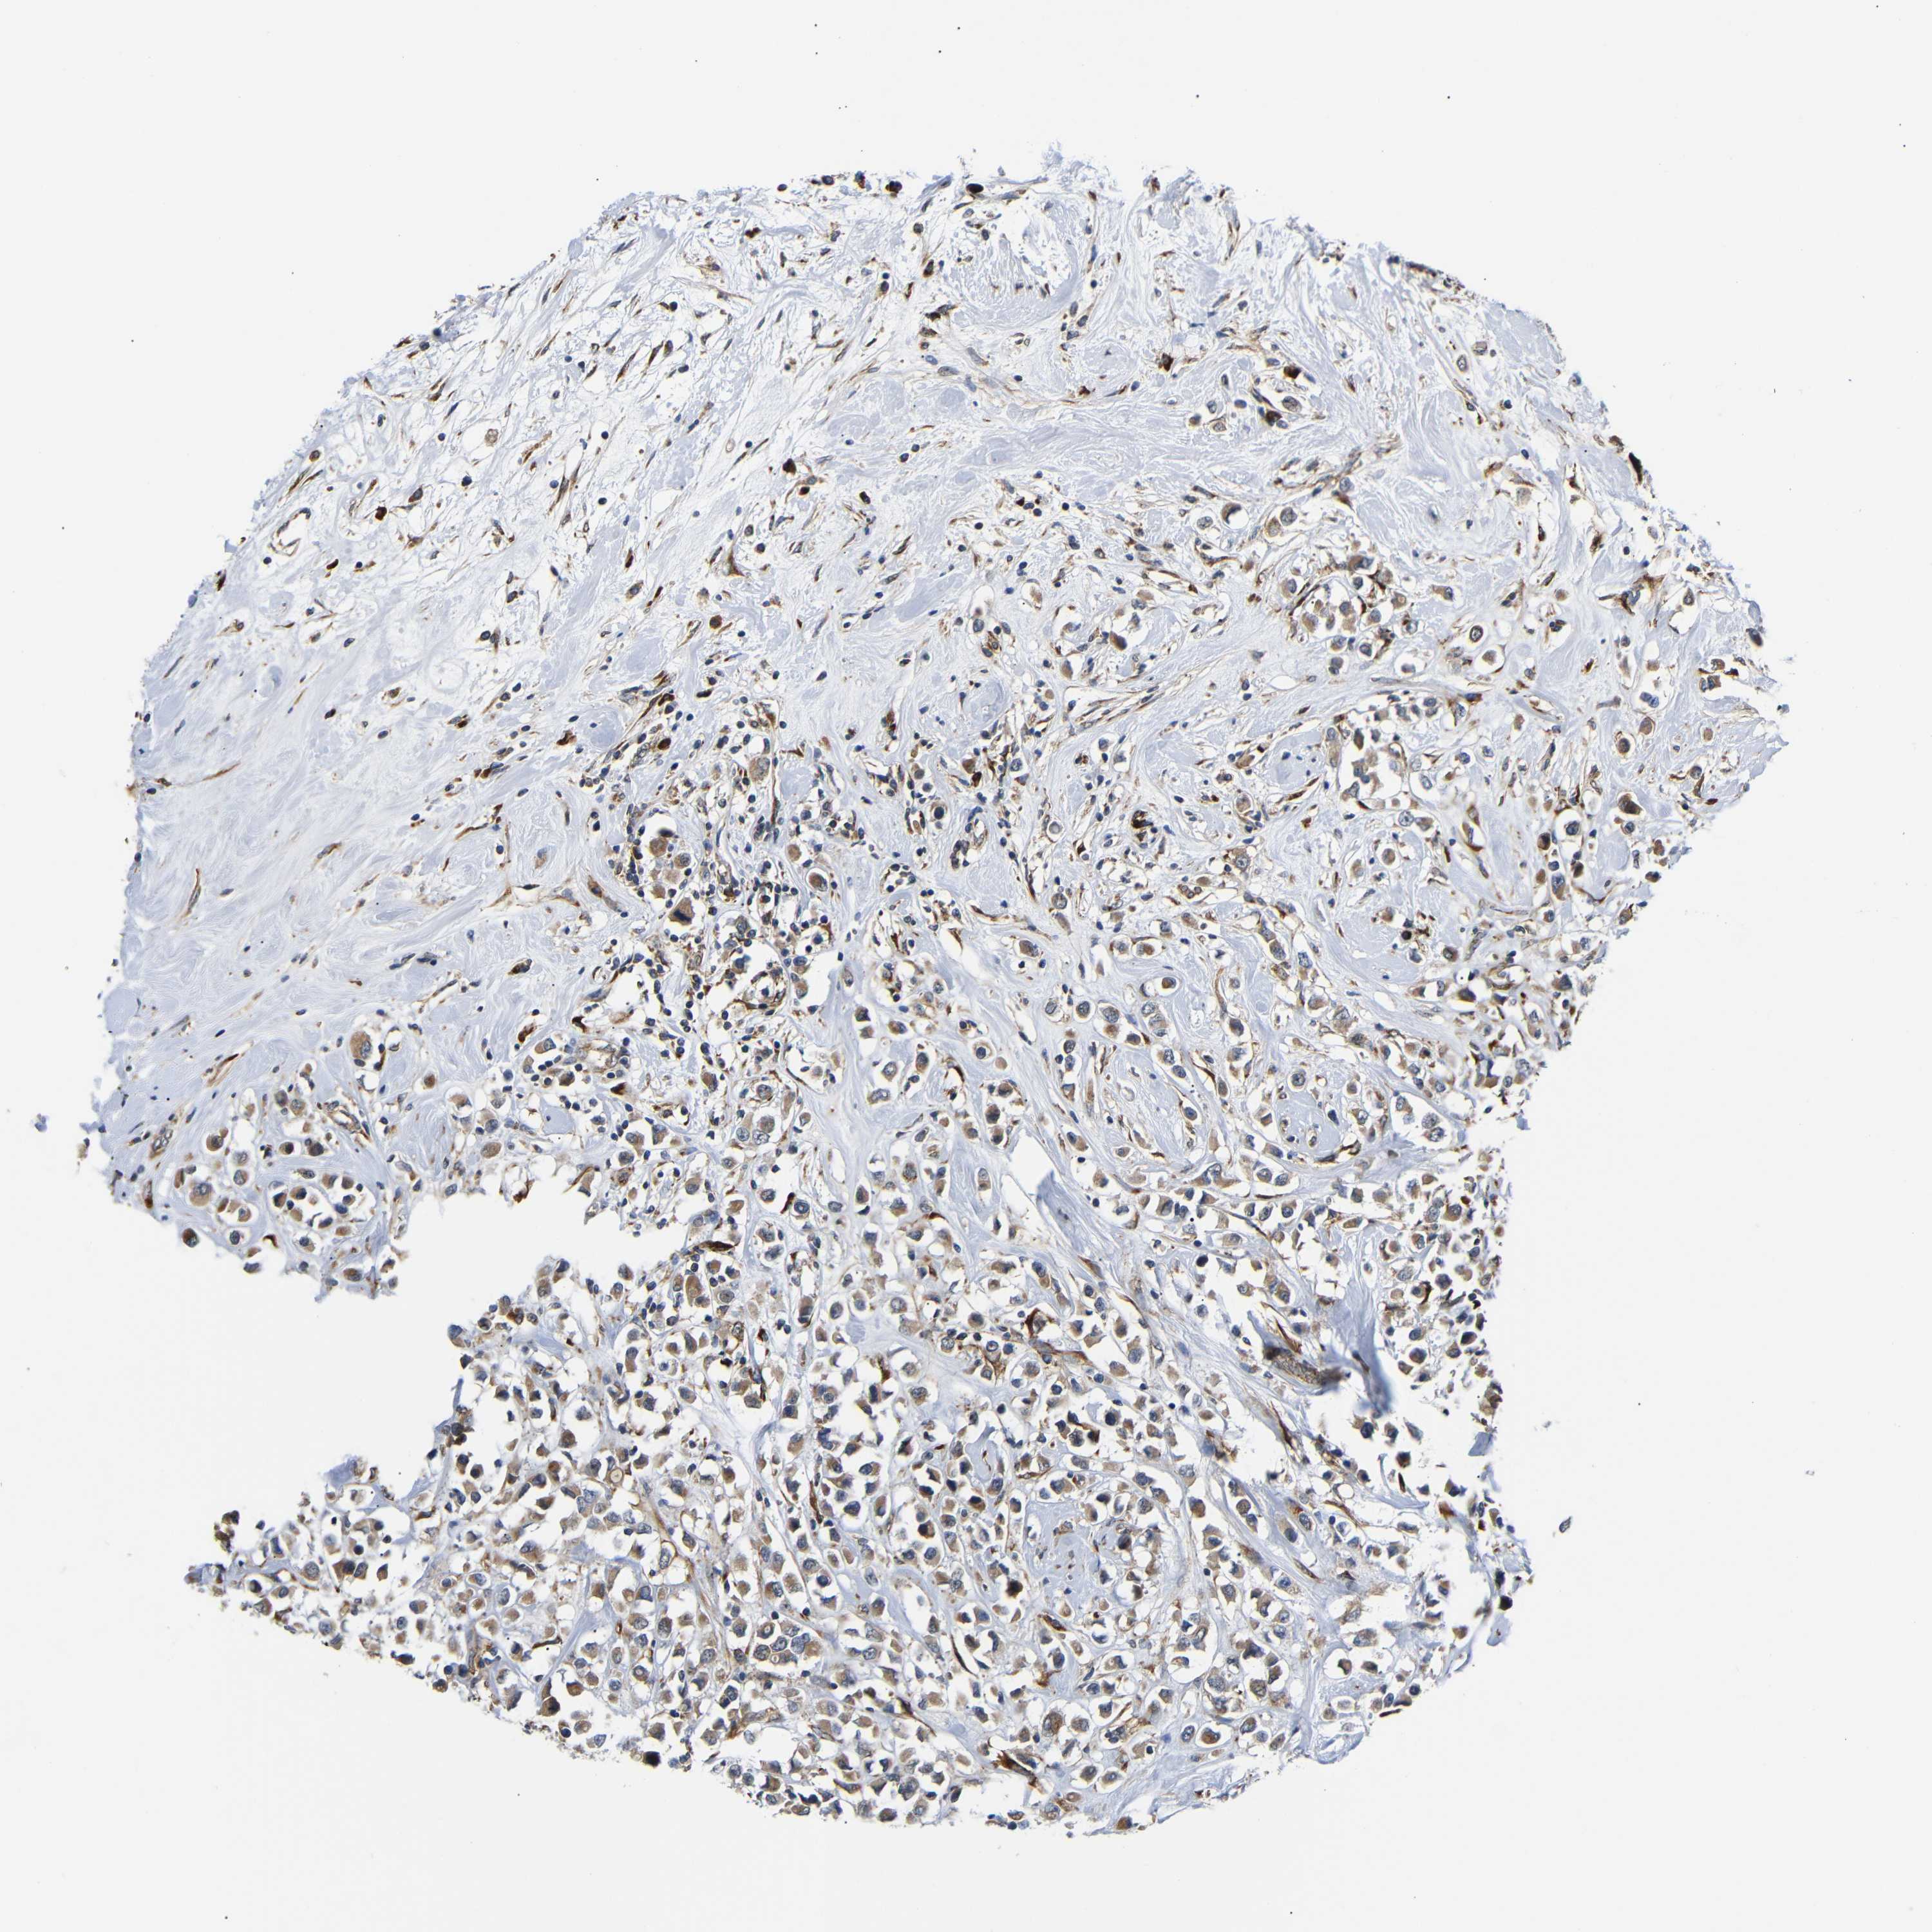

BRCA TCGA BRCA VALIDATION PROTEIN EXPRESSION